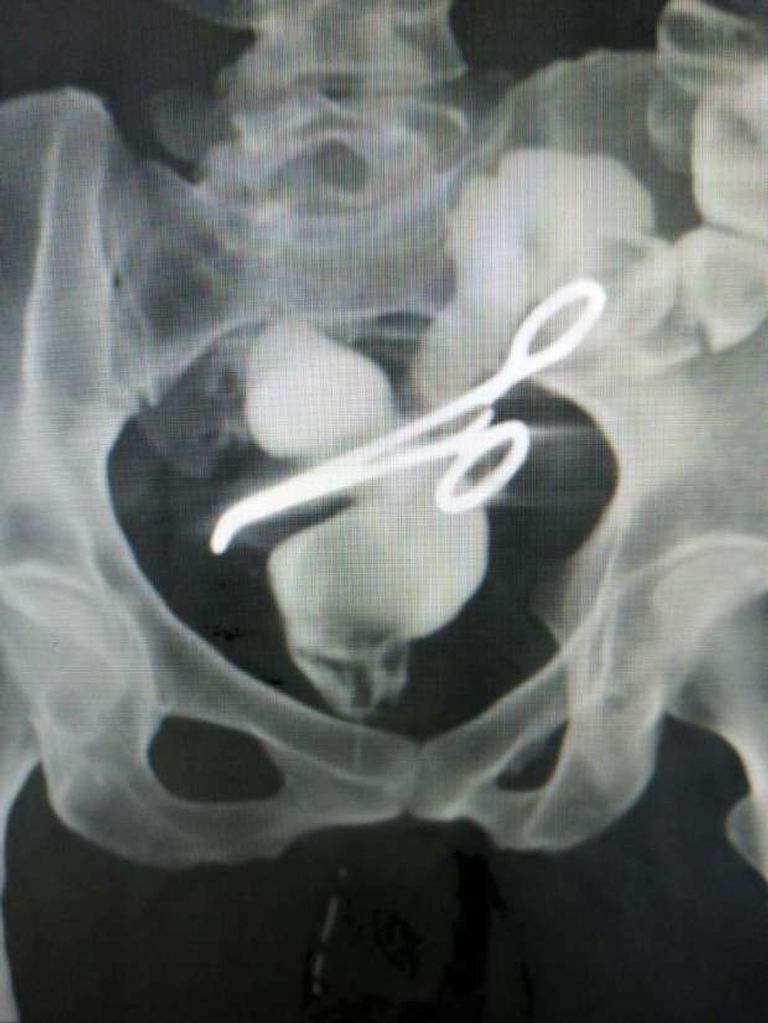

استخراج مقص جراحي منسي في بطن سيدة منذ 6 أعوام في مصر

ستخرج فريق طبي بجامعة

المنصورة

في

مصر

"مقص" ظل 6 أعوام داخل بطن سيدة بعد عملية جراحة استمرت 5 ساعات ومعاناة وآلام مبرحة.

أجرت السيدة "ن.ع"، البالغة من العمر 47 سنة، ولادة

قيصرية

في 2017، وظلت تعاني من آلام مبرحة بالحوض منذ شهر أذار 2023، بعدما حدث لها ناسور شرجي مهبلي.

حضرت السيدة للعيادة الخارجية بمركز جراحة الجهاز الهضمي، وقابلت الدكتور

أمجد فؤاد

رئيس أقسام الجراحة بكلية الطب

جامعة المنصورة

، وتم الكشف على الحالة فوجد أن بها شيئًا غريبًا وغير معتاد ببطنها، فأجرى عليها أشعة ومناظير وفحوصات، فتبين وجود جسم معدني بمنطقة الحوض.

شرحت السيدة أنها أجريت الجراحة القيصرية الخامسة لها في 2017، وكانت صعبة للغاية وحدث لها نزيف حاد وتهتك بالرحم، فقام الأطباء باستئصال الرحم لإنقاذ حياتها.

وأوضحت السيدة أنها مارست حياتها بشكل طبيعي حتى عام 2023، فشعرت بآلام بالبطن والحوض، ووجدت إفرازات شبيهة بالبراز تخرج من منطقة المهبل، ولما قامت بالكشف على حالتها تبين وجود جسم معدني.

خضعت السيدة لعملية تحضير مكثفة وتدقيق في

مركز جراحة الجهاز الهضمي

بجامعة

، فتبين وجود ناسور بين المستقيم والمهبل، بسبب وجود مقص أصاب القولون والمستقيم والمثانة وعنق الرحم.

تم إخراج المقص واسئتصال الأجزاء المصابة في جراحة مطولة استمرت 5 ساعات، بمشاركة فريق طبي كبير.